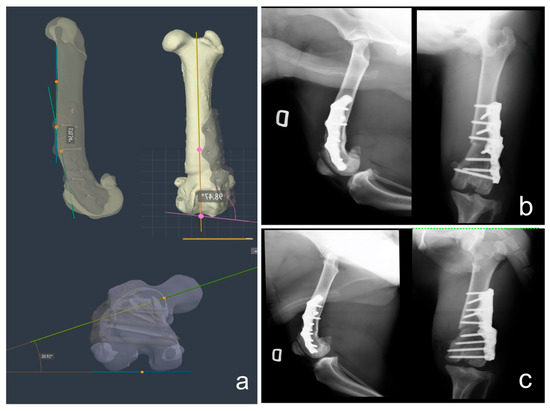

2.2. CT Scan Acquisition and Deformity 3D Measurements

2.3. Virtual Surgery, Patient-Specific Osteotomy Guide and Titanium Plate Design

| 1 | R | 83° | 94° | 98° | 158° | 170° | 170° | 25° | 20° | 20° | CT | Mild Metatarsal rotation | CWO; TBR; LD; MER. |

| 1 | L | 82° | 94° | 98° | 156° | 170° | 169° | 29° | 20° | 20° | CT | Mild Metatarsal rotation | CWO; TBR; LD; MER. |

| 2 | R | 82° | 94° | 95° | 163° | 170° | 172° | 29° | 20° | 20° | CT | Mild Metatarsal rotation | CWO; TBR; LD; MER. |